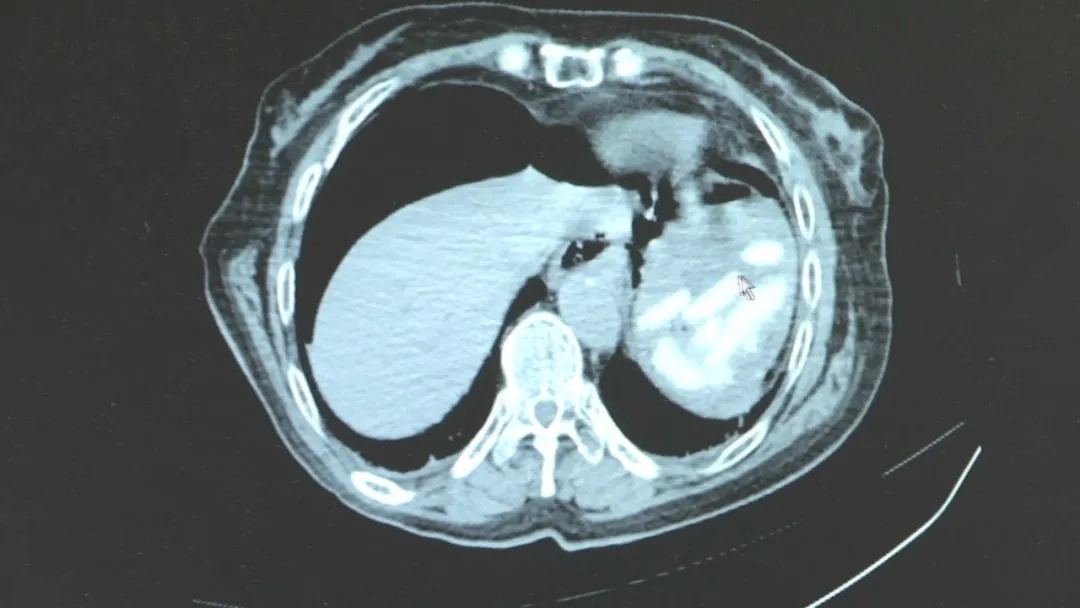

谁承想,CT影像一显,情况远比表面凶险:患者的胃部破裂,在胃小弯侧形成了约4厘米的破口,腹腔里存在大量积气体,更发现了大量尚未消化的年糕。医疗团队当机立断,将患者转入胃肠外科进行紧急手术。